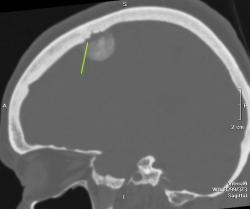

Полностью обызвествленная менингиома теменной области (красная стрелка). В прилегающей кости узурация (зеленые стрелки) и небольшой гиперостоз в виде клюва (голубая стрелка). Небольшой масс-эффект - крыша левого бокового желудочка поддавлена (желтая стрелка), субарахноидальные щели слева немного уже, чем справа. Перифокального отека нет - признак доброкачественности образования. Отек при менингиоме может развиться при очень больших размерах образования или при малигнизации. Пациентка жалуется на головные боли. На снимках черепа ничего необычного нет.